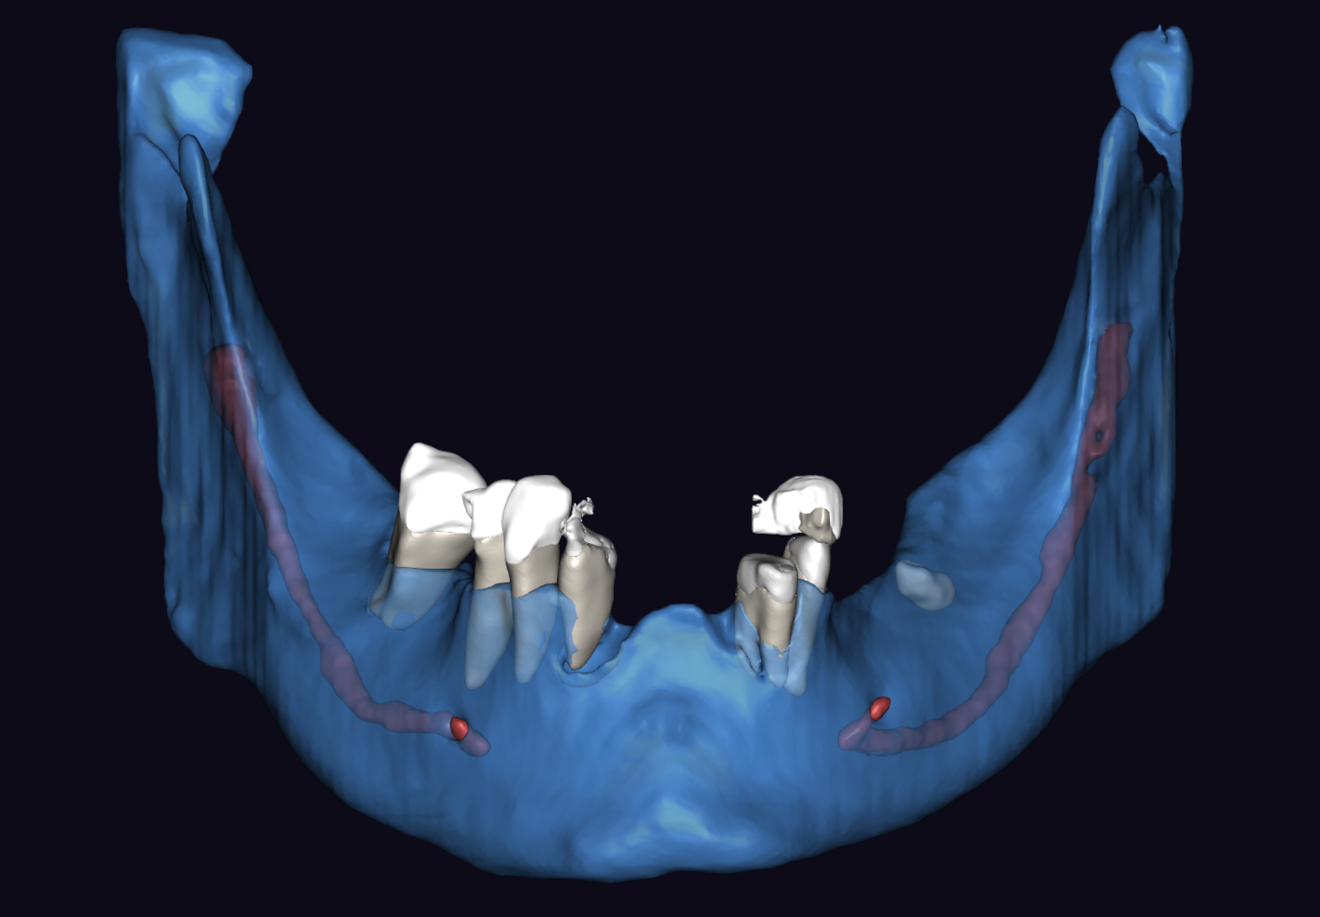

Figs. 3a & b: Segmented CBCT scan (a). Mandibular arch morphology after virtual teeth extractions (b).

Intra-oral examination revealed compromised mandibular dentition, an old fixed prothesis, missing posterior teeth on the left side, periodontal involvement and gingival inflammation. A panoramic radiograph was obtained, and the findings were reported to the patient (Figs. 1a & b; 2a & b). Both mandibular canines had visible periapical radiolucencies. A CBCT scan was performed for a more detailed assessment of the alveolar bone anatomy (Figs. 3a & b). Temporomandibular joint examination revealed no indication of dysfunction (crepitus, clicking or pain).